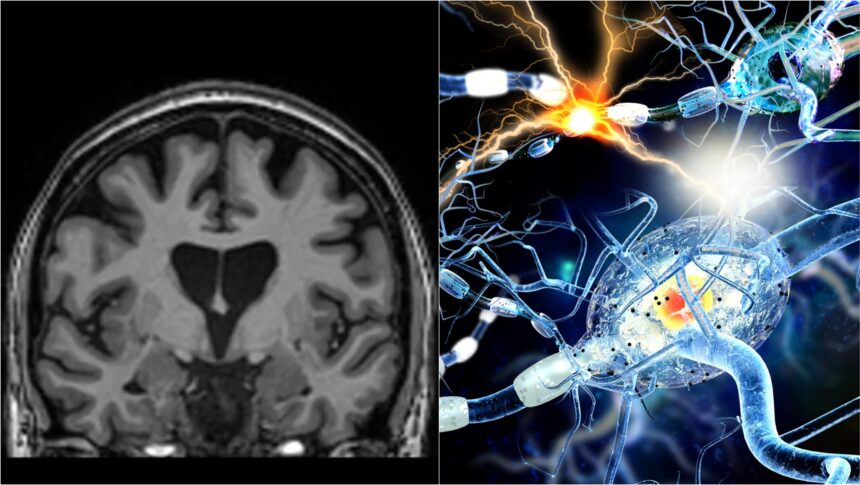

Una dintre cele mai devastatoare boli ereditare a fost tratată cu succes pentru prima dată, potrivit cercetătorilor de la UniQure, o companie de biotehnologie din Amsterdam. Experimentul lor a arătat o încetinire cu 75% a evoluției bolii Huntington la pacienții care au primit noul tratament ce presupune o tehnică genetică inovativă.